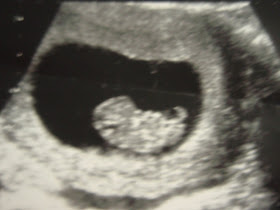

During an ultrasound you might see how your baby moves even though you. During this 9 weeks pregnant ultrasound you will see the foetus on the screen. Your baby is about the size of a peanut.

At 9 weeks pregnant morning sickness is peaking and you may be dealing with mood swings heartburn and other pregnancy symptomsmeanwhile your baby is growing looking more human and even moving around. The first two months of pregnancy are behind you. You will be able to view a detailed gestational sac yolk sac and the foetal pole.

Read more about its process abnormalities and more. An ultrasound will show the heartbeat of your baby now it makes about 130 150 beats per minute. When it comes to pregnancy symptoms you may feel like youve already reached your limit at 9 weeks pregnant.